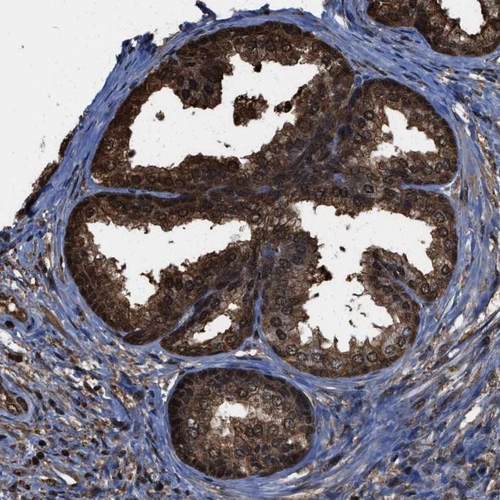

Immunohistochemical staining of human prostate shows nuclear and cytoplasmic positivity in glandular cells.